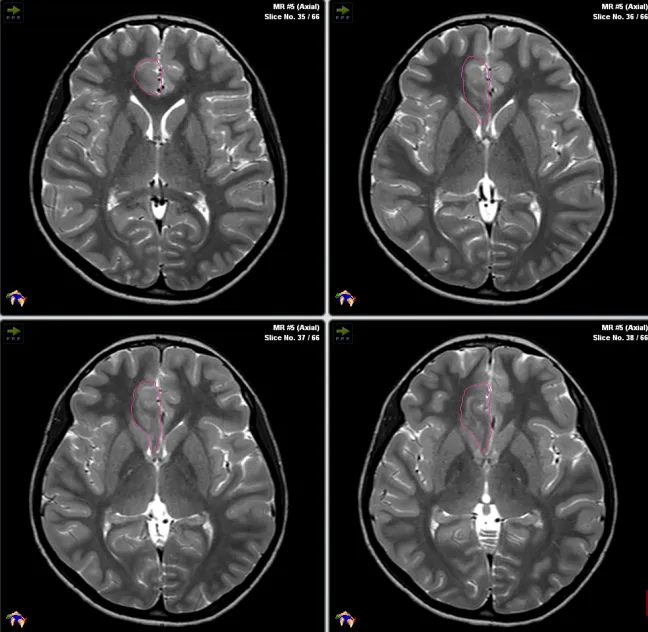

Rutka教授案例分享:局灶性皮质发育不良,复发癫痫

一名患有额叶癫痫的12岁男孩,伴有运动机能亢进的癫痫发作,神经成像检查结果显示:右侧额内侧下基底病变,他接受了开颅右额叶病灶切除术,病理资料显示为局灶性皮质发育不良(FCD),术后三个月无癫痫发作。

不幸的是,三个月后他的癫痫复发了,但Rutka教授不希望孩子在短时间内再次接受开颅手术,因此与患者家属深入沟通后决定为其进行激光间质热疗(LITT)。

Rutka教授和他的团队正在为其手术

术后男孩便没有癫痫发作了,而且近期随访显示其生长发育和智力发育正常,且癫痫并未复发。